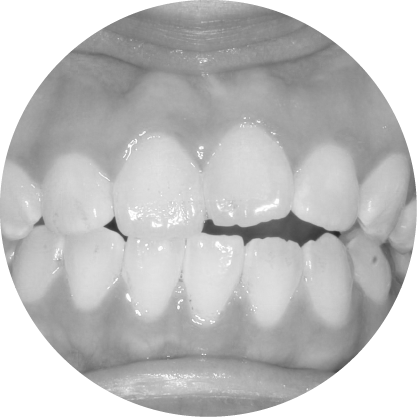

ตัวอย่างในชีวิตจริง

Crossbite teeth model – misalignment of dental arches

การสบฟันแบบไขว้ (Scissor Bite)

การแก้ไขฟันสบไขว้ เพื่อการสบฟันที่สมมาตร

ฟันสบไขว้คือภาวะที่ฟันบนหนึ่งซี่หรือมากกว่าสบอยู่ด้านในของฟันล่าง ซึ่งอาจทำให้เกิดการสึกของฟันอย่างไม่เท่ากันหรือปัญหาข้อต่อขากรรไกร การจัดฟันช่วยปรับแนวการสบฟันให้ถูกต้อง เพื่อประสิทธิภาพในการใช้งานที่ดีขึ้นและความสมดุลของใบหน้า